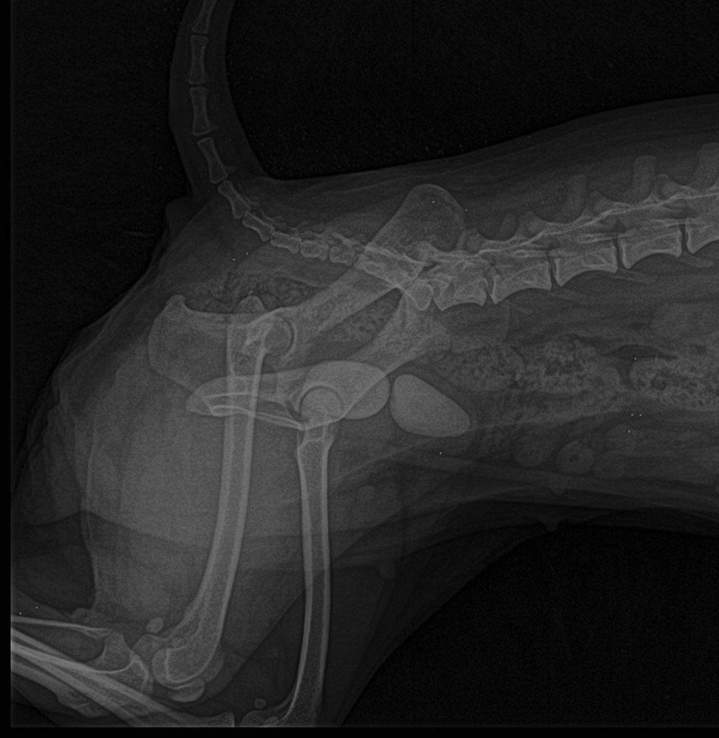

Une radiographie pourra être envisagée afin de mettre en évidence des calculs dans la vessie ou dans l’urètre. Et une échographie nous permettra de voir des signes de cystite ou des calculs non visualisables à la radiographie.

À court terme, il faudra très rapidement lever l’obstruction. Un sondage urinaire sera alors réalisé sous anesthésie générale. La sonde sera laissée en place pendant plusieurs jours afin de vidanger la vessie et de la rincer pour évacuer tous les calculs de petite taille présents dans la vessie.

En cas de calculs impossible à dissoudre ou en cas de calculs de grande taille, une intervention chirurgicale (cystotomie) est parfois nécessaire pour les retirer de la vessie.

Lorsque des molaires sont responsables, on peut rencontrer différentes expressions de leur croissance erratique. Le diagnostic précis ne peut se faire que sous anesthésie. Des pointes ou des ponts seront à couper, parfois on peut rencontrer des abcès qui se curent toutefois très difficilement. Ces abcès sont souvent très agressifs et peuvent envahir les tissus osseux. Le but est de pouvoir les exciser dans leur totalité ainsi que la ou les dents responsables. Une radiographie est souvent indispensable. Le pronostic de ces abcès est réservé.

Les radiographies de la tête, même chez un rongeur ou lapin sain, peuvent de manière générale indiquer une malocclusion. Le risque de savoir si celle-ci risque de provoquer des suites indésirables est plus difficile à prédire.